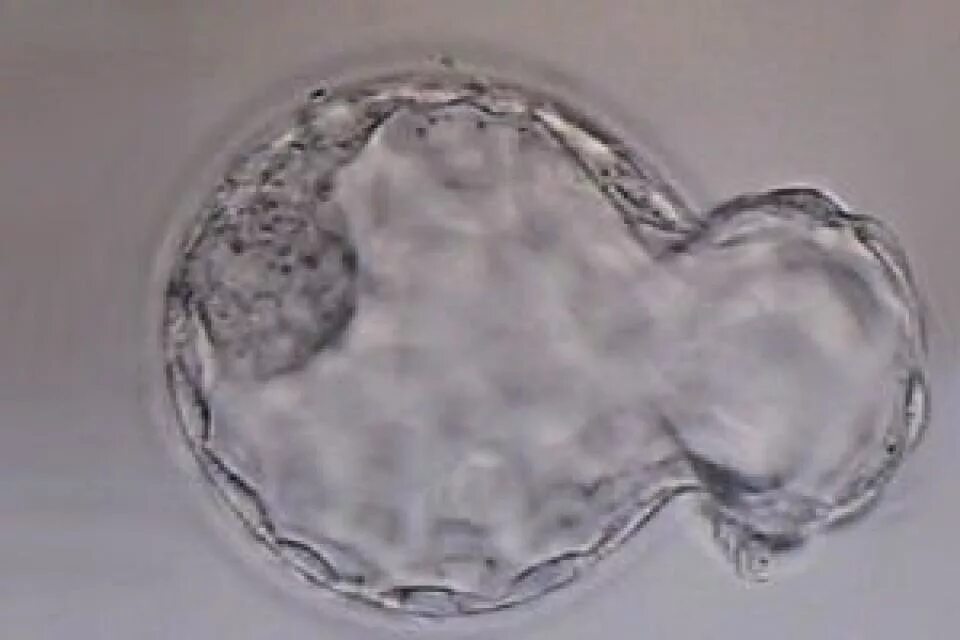

Процесс отделения эмбриона от желтка начинается